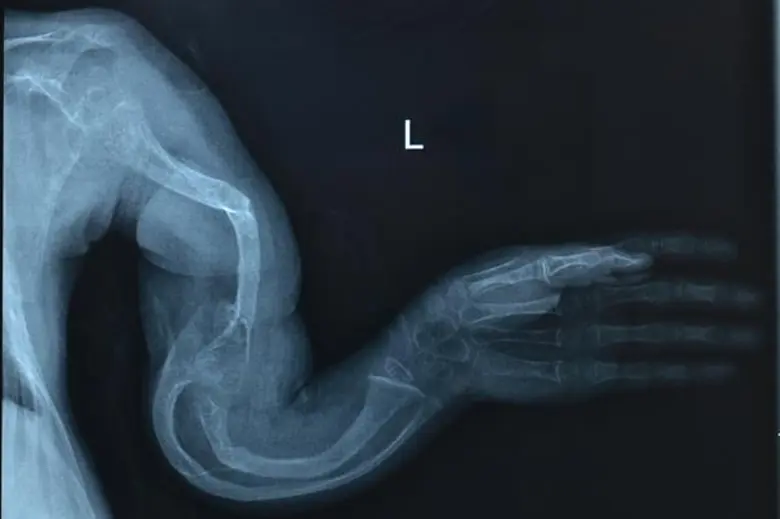

เกิดจากความผิดปกติของสารพันธุกรรม ก่อให้เกิดความผิดปกติได้ตั้งแต่หัวจรดเท้า เพราะการสร้างและการทำงานของอวัยวะทุกส่วนของเราถูกกำหนดด้วยรหัสพันธุกรรม (Genetic code) ทั้งสิ้น โดยคาดว่าประชากรไทยทั้งประเทศราว 8% หรือมากกว่า 5 ล้านคน จะเป็นโรคใดโรคหนึ่งของโรคหายาก ซึ่งโรคหายากนี้อาจแสดงอาการออกตั้งแต่อายุเท่าใดก็ได้ ขั้นแรกที่จะนำไปสู่การรักษาที่ได้ผลดีที่สุดคือ

ผลจากงานวิจัยทำให้พบยีนก่อโรคชนิดใหม่ของโรคหายากมากมาย เช่น การพบการกลายพันธุ์ในยีน SATB2 ใน Glass syndrome (อาการพัฒนาการล่าช้า) หรือ การค้นพบเป็นครั้งแรกว่ายีน DLX5 และ DLX6 ในเซลล์กระดูกของคนปกติเป็น Imprinted gene (ศึกษากลไกการเกิดโรคของภาวะนิ้วไม่ครบ) รวมถึงก่อประโยชน์ต่อการรักษาโรคทั่วไปมากมาย

หลายครั้งที่ผลจากงานวิจัยเพื่อตอบโจทย์การรักษาโรคหายากถูกนำไปใช้ประโยชน์เพื่อการรักษาผู้ป่วยที่ป่วยเป็นโรคทั่วไป เนื่องจากโรคหายากจะเกิดจากการกลายพันธุ์ของยีนๆหนึ่งที่ส่งผลกระทบสูงหากเทียบกับโรคทั่วไปที่มีการกลายพันธุ์ของยีนตัวนี้เช่นกันแต่เป็นชนิดที่ส่งผลต่ำกว่า ต้องร่วมกับการกลายพันธุ์ของยีนอื่นหรือปัจจัยจากสิ่งแวดล้อมจึงจะทำให้เกิดอาการ ตัวอย่างจากงานวิจัยของกลุ่มเรา คือการค้นพบยีน MBTPS2 เป็นยีนก่อโรคตัวใหม่ที่ทำให้เกิดโรคกระดูกเปราะหักง่าย ซึ่งเกิดกับครอบครัวของคนไข้ชาวไทยเป็นครั้งแรกของโลกนอกจากสามารถหาสาเหตุเพื่อดูแลผู้ป่วยครอบครัวนี้ได้แล้ว ความรู้ยังอาจสามารถนำไปต่อยอดสู่แนวทางการรักษาโรคกระดูกพรุน ซึ่งอาจจะเป็นประโยชน์ต่อสตรีวัยหมดประจำเดือนได้อีกด้วย